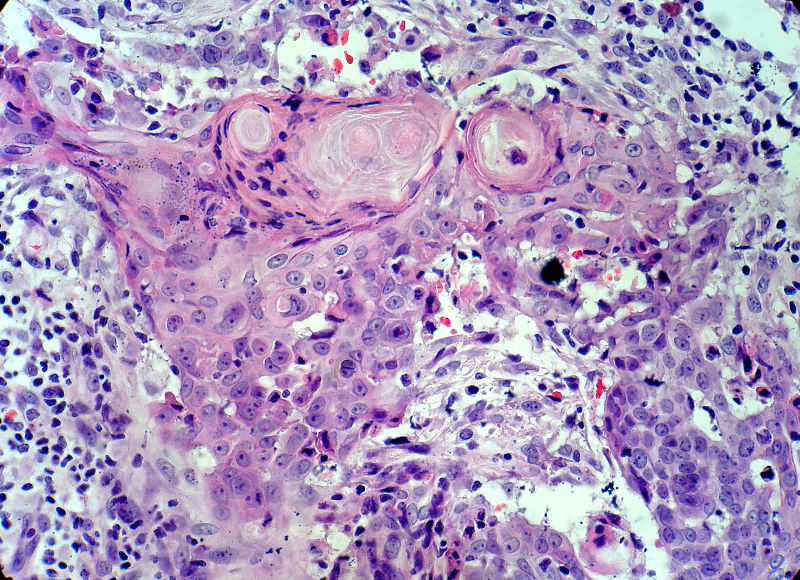

男,49岁,后枕部肿物3年,偶有破溃出血。

大体:皮肤半球形隆起,大小约2.3×2厘米,高出皮表0.8厘米,切面灰白,质地细腻。

似乎既有腺样结构,也有角化珠形成,还有细胞团内的粉刺样坏死。